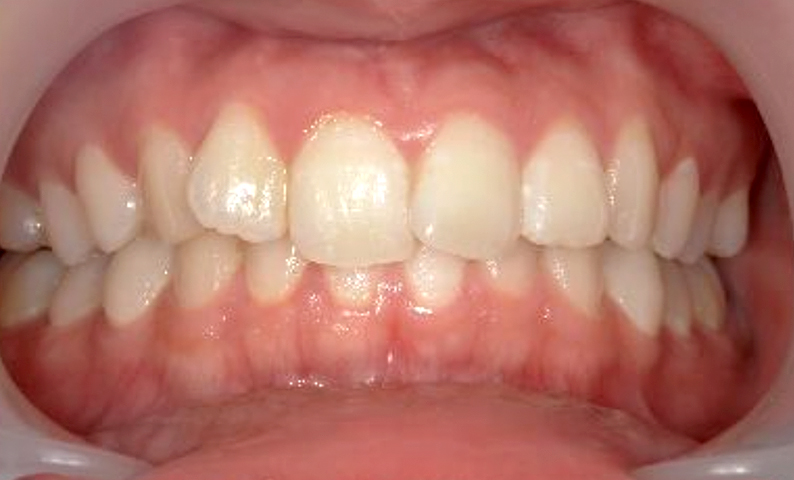

症例_025 上顎だけの部分矯正

治療期間:7ヶ月金額:30万円+税女性前歯のガタガタ上の前歯だけ

| Before | After |